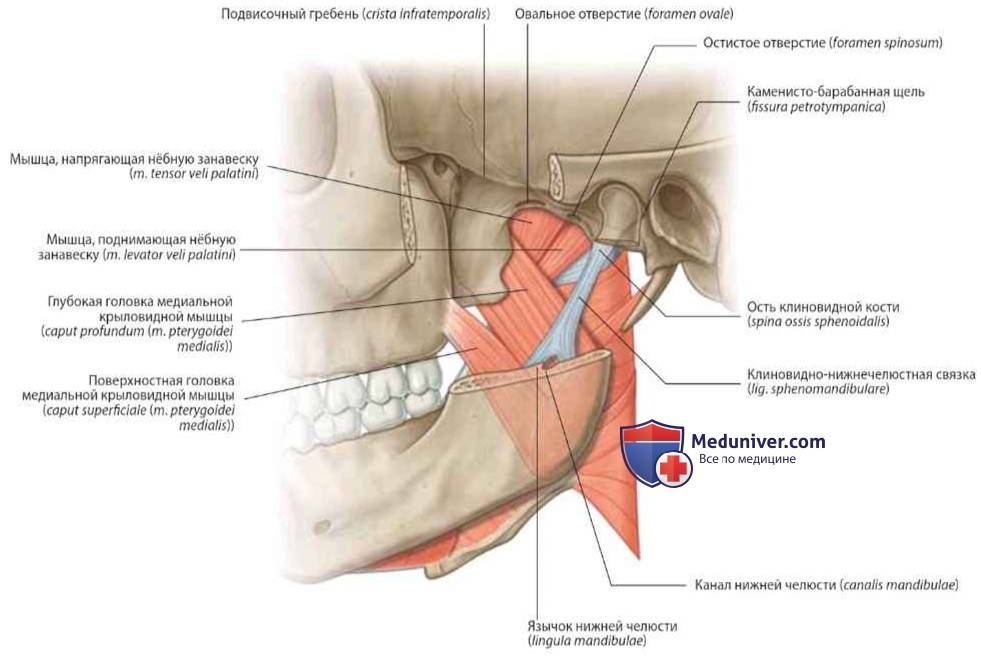

Анатомические особенности: фотографии ямок черепа, височной и подвисочной крылонебной